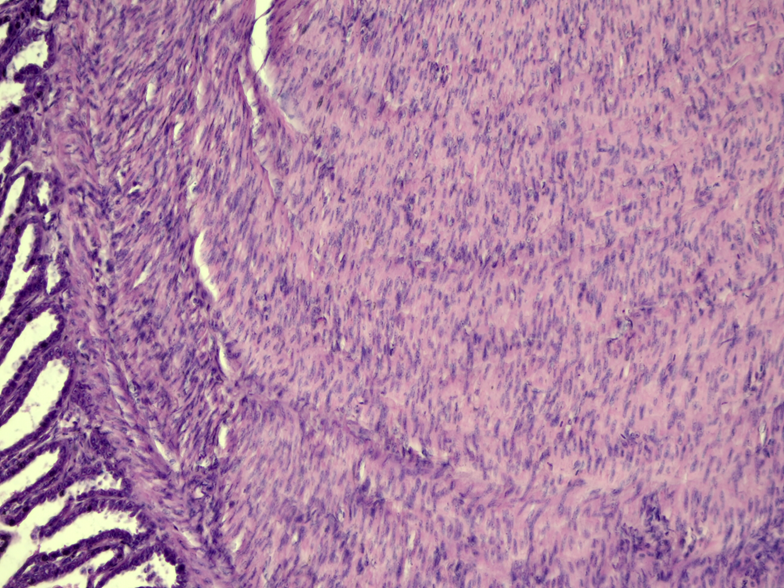

The radiographic study did not refer conclusive results. Post-mortem evaluation revealed small intestine with marked wall thickening. In serial sections of the small intestine stained with hematoxylin-eosin (HyE), a thickened longitudinal muscular tunic was evaluated, with palisade proliferation, slightly disorganized, of parallel spindle cells with a central nucleus and homogeneous eosinophilic cytoplasm (Fig. 1 y 2). Lamina propria and submucosa with marked congestion in blood vessels. No mitotic figures or cellular atypia were observed. Histopathological diagnosis referred intestinal leiomyoma.

Figure 2: Small Intestine. Longitudinal muscular tunic with proliferation of smooth muscle fibers and compression of the submucosal tunic. H-E. 40x